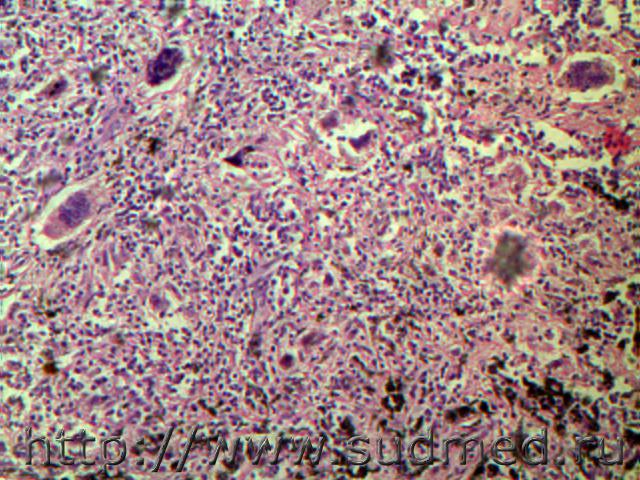

Ж.56 лет. Трансторакальная видеобиопсия бифуркационного лимфатического узла.По гистокартине ввиду отсутствия казеозного некроза, разной формы штампованностью гранулем с отложением эозинофилно-гиалиноподобной массы, наличием многоядерных гигантских клеток по типу инородных тел,выраженной склеротической стромой с угольным пигментом и периартеритом был выставлен - Саркоидозная гранулема л/у легких.